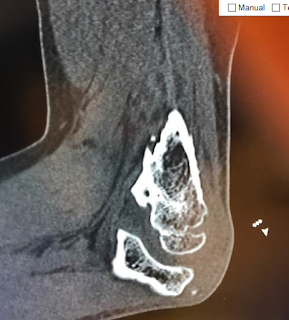

This patient presented with a chronic anterior dislocation of the humeral head after a proximal humerus fracture, the humeral head was malunited in the subscapularis recess. Osteotomy of the humeral head was required to remove the bone from the anterior glenoid. The fracture was addressed with hemiarthroplasty and repair of the tuberosities. The use of a stem that provides a "window" for proximal bone grafting, the removal of the cement circumferentially from the proximal stem during implantation, and the stable suture repair of the tuberosities with Fiberwire provided a good outcome with union of the tuberosities. The anterior inferior subluxation of the humeral head persisted for 6 months but eventually it was resolved. Contrary to the belief that this is the result of a "fracture hematoma" it seems that this finding is associated with muscle atony or contusion of the rotator cuff or axillary nerve neuropraxia. X-rays are shown below.